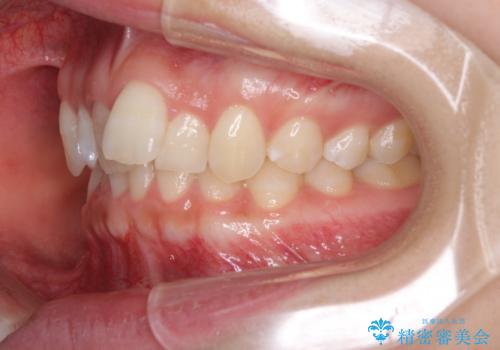

- 前歯のデコボコ気になるとのことで来院された患者様です。

下顎骨が上顎骨に対して右側にシフトしており、さらに下顎が後方に位置しているため、非常に強い咬合力で食いしばっている状態でした。

上下顎ともに歯列全体の後方移動とIPR(歯と歯の間を削る)によってデコボコが解消するように設計し、インビザラインにより治療を行うこととしました。

強い咬合力による臼歯部の噛みにくさと、それに伴う歯の移動の鈍さに悩まされ、非常に長い期間を要することとなりました。

上下正中位置は、治療開始時よりは改善したものの、ここが限界であろうというところでのゴールとなりました。

下顎前歯の大半が隠れている状態ですが、左右への歯ぎしりはスムーズに行うことができ、就寝時には後戻り防止も兼ねて、食いしばり対策としてマウスピースの使用を継続するようお願いしております。